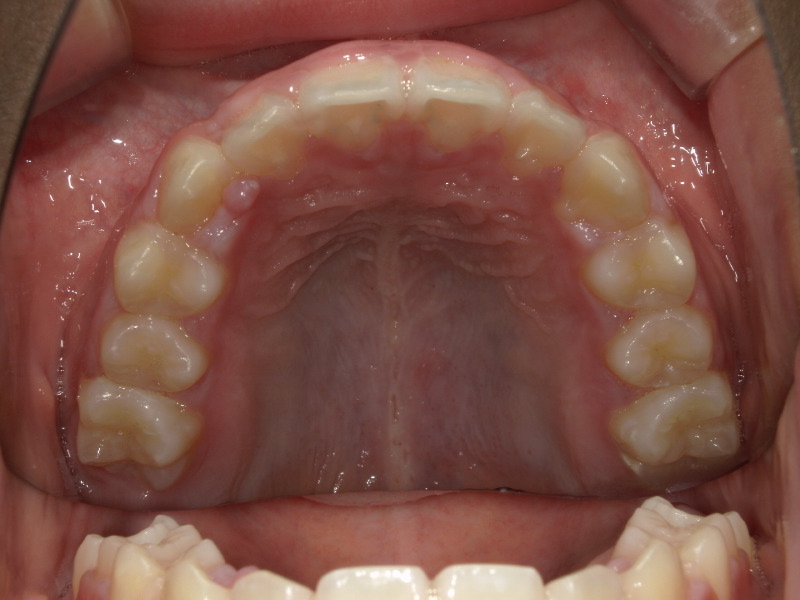

併用の装置、マウスピースの継続で歯はかなり綺麗になりました。

残っているアクティビティーもしっかりと行なってもらい、アクティビティーも卒業へ

最終的に癖がないかも検査したり、永久歯への生え変わりまでは経過観察も来院をお願いしているのですが、いつもお口を楽に閉じていられるようになりました。

正しい成長へ

顎が正しく前方へ成長すれば、気道も広がります。

全て緑になりとても大きくなりました。

今は卒業していますが、いつもお鼻の呼吸を覚えていてね。